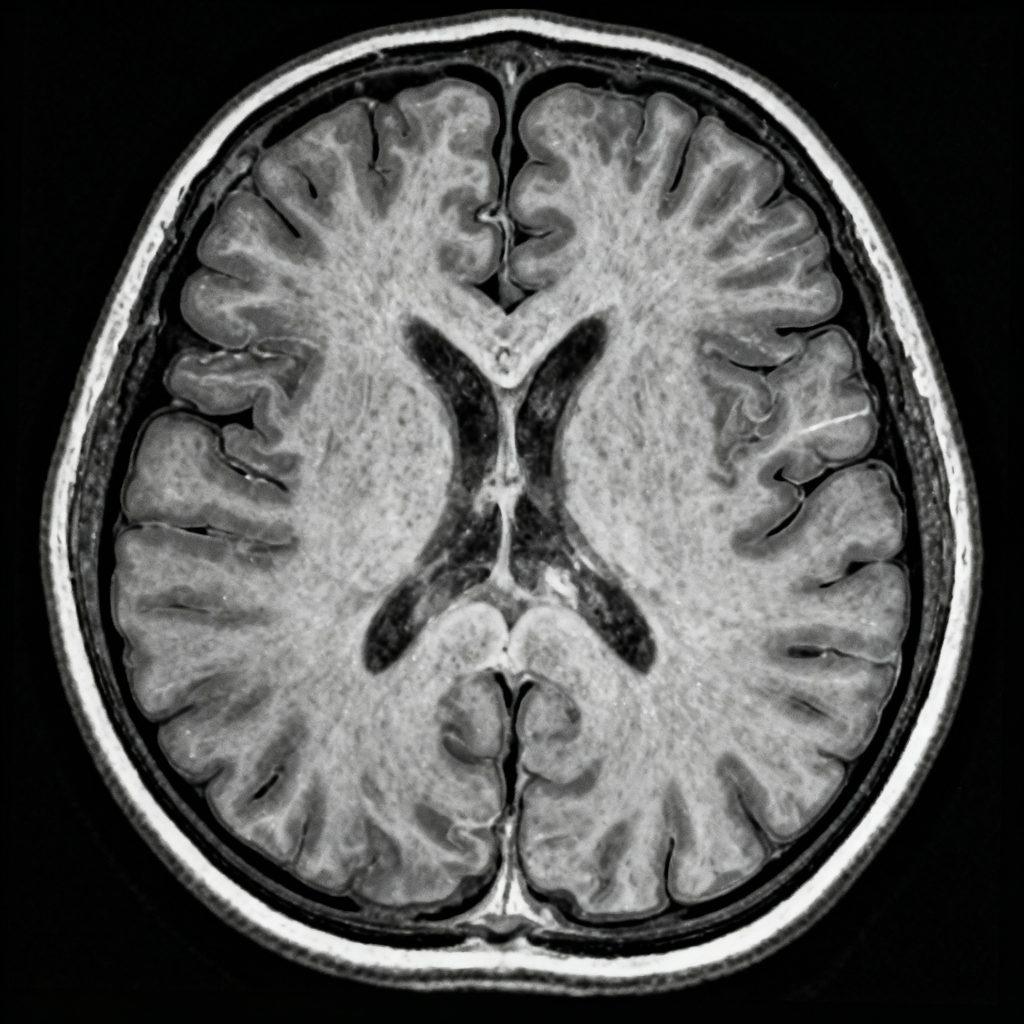

更年期不僅影響女性荷爾蒙和生理狀態,連大腦也會跟著改變?科學家發現,在更年期期間,大腦某些區域的體積會縮小,白質(神經訊息傳遞的主要通道)也可能出現損傷,導致記憶力下降、注意力變差、思考變慢等現象,不過最新研究指出,這些變化並非無法逆轉,大腦隨時間仍具備一定的適應與恢復能力。

研究指出,更年期與「灰質體積下降」有關,特別影響掌管記憶、思考與決策的額葉、顳葉及海馬迴。這些區域的萎縮會導致語言記憶力和空間判斷能力變差。

MRI(磁振造影)影像也發現,女性在更年期期間常出現白質高亮點(white matter hyperintensities),這些影像異常可能反映出細微的組織損傷。尤其是早發性更年期或經常有熱潮紅的女性,這類現象更為明顯,可能與腦部血流減少有關。若問題持續惡化,可能增加中風、失智及情緒變化的風險。

好消息是,部分研究顯示在更年期結束後,大腦灰質體積有機會部分恢復,顯示出神經具有「可塑性」,也就是能重新建立新的連結。研究也發現,更年期過渡期女性的大腦中雌激素受體密度上升,顯示大腦似乎在試圖彌補激素下降的影響。